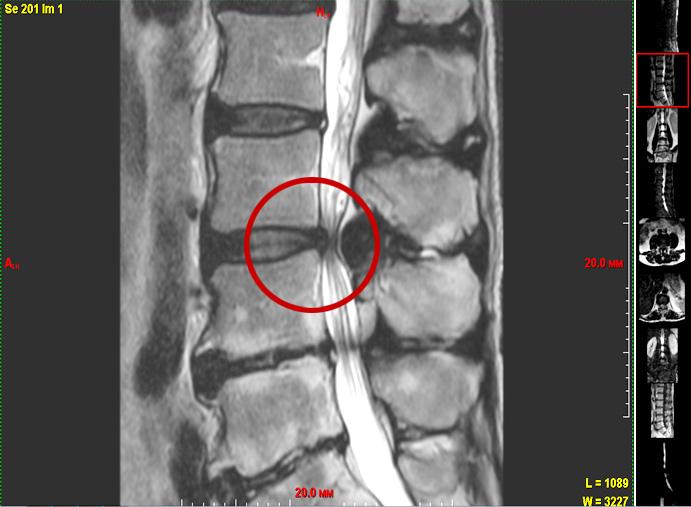

Говоря о рецидивах, хочу отметить, что очень сложно отличить, это рецидив или рубцовый процесс после операции. На МРТ разницы практически нет. Когда у пациента, у которого уже была операция, на том же уровне мы находим какие-нибудь «штуки», если нет строгих показаний к новой операции, мы пробуем консервативное лечение. Получили результат — замечательно. Потому что, допустим, в заключении МРТ нам написали рецидив, большой секвестр (участок омертвевшей ткани — прим. авт.), а мы заходим и, кроме рубцов, ничего не находим. Естественно, делаем декомпрессию, все рубцы рассекаем и прочее. Но если у человека уже пошло рубцевание, каждая последующая операция будет добавлять еще рубцов. Это склонность к келоидозу. Поэтому каждый раз, когда мы думаем, предлагать человеку операцию или нет, пытаемся оценить все возможные варианты. Если есть малейший шанс обойтись без операции, мы не бежим в операционную.